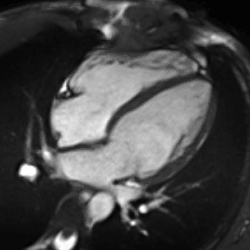

Late gadolinium enhancement

Gadolinium-based contrast agents are administered intravenously and delayed imaging is performed at least 10 minutes later to achieve optimum contrast between normal and infarcted myocardium. An inversion recovery (IR) sequence is used to null the signal from normal myocardium. Myocardial viability can be assessed by the degree of transmural enhancement. Cardiomyopathic, inflammatory and infiltrative diseases may also have distinctive patterns of non-ischemic LGE.[22][23]